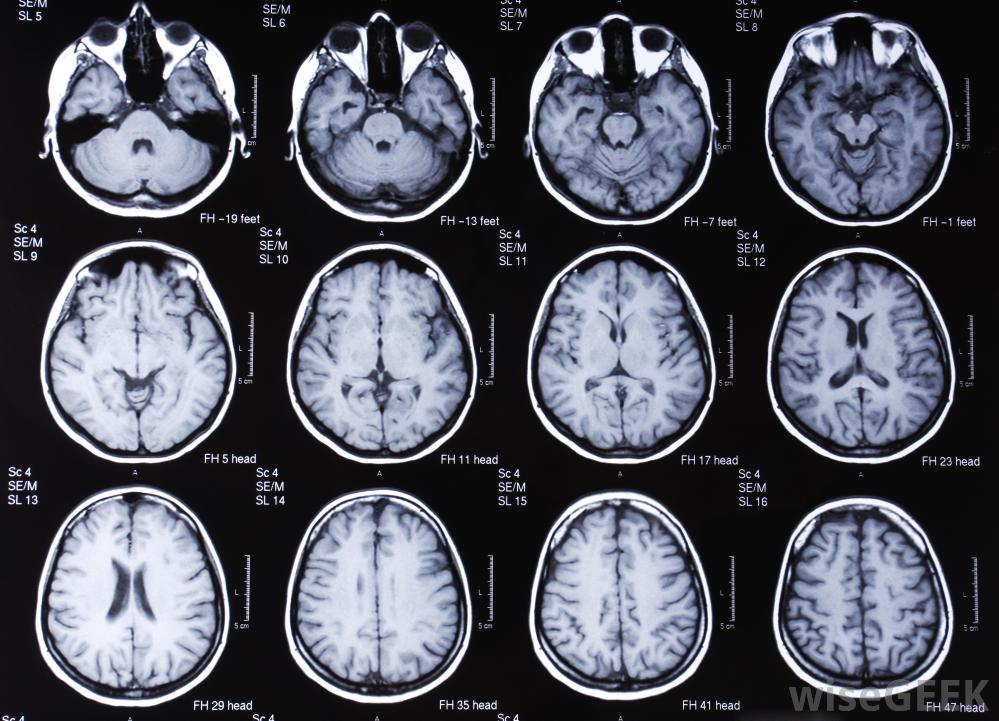

И вот наступил тот день, который изменил все. Которому ничего не предвещало. Как обычно проснулся, умылся, поговорил с мамой и сел обедать. Во время обеда замечаю, что моя рука ведёт себя странно и я не могу контролировать. Отключаюсь и виду перед собой перепуганных родителей. Сначала я не придал значения этому событию, но родители настояли пойти к врачу. Терапевт сказал, что скорее всего ничего серьёзного и просто скачки давления, но на всякий случай отправил к неврологу. Невролог отправил на мрт. Мрт показало объемное кистозно-солидное образование.

Спустя несколько дней консультация у нейрохирурга, до которой ещё была надежда, что ничего серьёзного нет. Но он лишь смог подтвердить, что это онкология. Единственное, что он смог сказать обнадёживающее, так это то, что на мрт опухоль выглядит как доброкачественная. Но до гистологического исследования это лишь предположение.